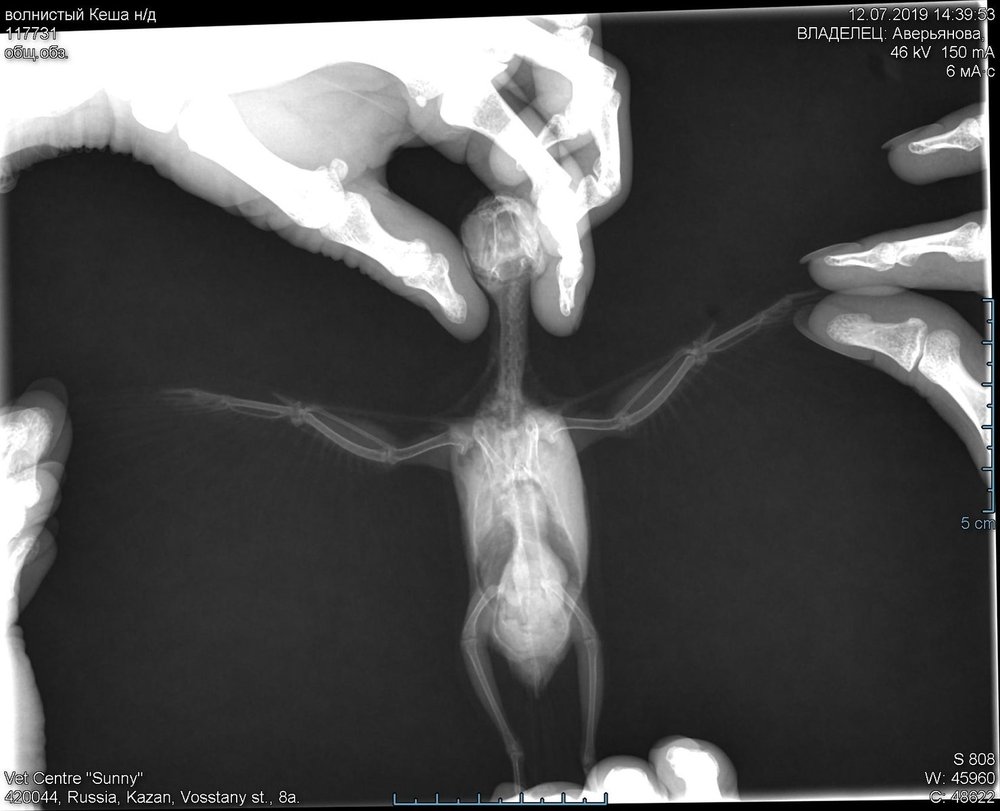

Кузяныч Опубликовано 9 июля, 2019 #18 Опубликовано 9 июля, 2019 ...Попугайчик в возрасте с запущенной липомой и / или дополнительными неприятностями под ней.. Жидкий помёт в течение такого продолжительного срока -- либо вторичная инфекция, либо нарушение обмена веществ, либо результат сдавливания пищеварительных органов новообразованием... Форма тела птички нарушена -- брюшная область намного шире области зоба -- неправильная грушевидная форма.. Этому попугайчику противопоказаны любые витамины, проростки, зелень (траву с улицы полностью следует исключить), кукуруза, продукты животного происхождения. Яблоко так же не давайте -- оно поддерживает кислую и сладкую среду, которую любят грибки. Споробактерин проверьте на состав что в нём ещё кроме культур бациллус субтиллис. В идеале вам следует приобрести споровит и энтерол, давая их 2:1 соответственно, доза -- 1 булавочная головка дважды в сутки (последний раз на ночь). Ищите детский элькарнитин (элькар) -- добавляйте его в поилку из расчёта 1 капля на каждое 10мл воды. Если начали курс глюконата кальция (1,5мл на 50мл воды) -- пропейте неделю, после чего начинайте курс элькра. Это для борьбы с липомой -- вздутием на животе. Возможно, ещё не слишком поздно... Для постановки диагноза попугайчику вам требуется: полнаяразвёрнутая копрограмма помёта попугайчика (бак.посев при обнаружении йодофильной флоры / палочек), микроскопия смыва из зоба (в помёте может ничего не выявиться, а в зобе полно), рентген в прямой и боковой проекциях. Тогда мы увидим, есть ли у птички грибы / бактерии / нарушения обмена веществ. И сможем оценить что кроется под вздутием, каково состояние печени, зоба и органов дыхания этого волнистика. Это -- единственный кратчайший путь к наиболе эффективному лечению. Обсудите возможность проведения обозначенных исследований с вашим врачом. Газовый наркоз, если попугайчик не ручной, крайне желателен, особенно чтобы снимки рентгена были чёткими!

Ксения2702 Опубликовано 12 июля, 2019 Автор #21 Опубликовано 12 июля, 2019 (изменено) @Кузяныч были сегодня повторно на осмотре и делали рентген. Врач сказал, что увеличена печень. Но не критично. Почему нельзя зелень? Орнитолог наоборот посоветовал разнообразить питание. Изменено 12 июля, 2019 пользователем Ксения2702

Кузяныч Опубликовано 14 июля, 2019 #22 Опубликовано 14 июля, 2019 Зелень и витамины нельзя при подозрении на новообразования, потому что подобные вещества ускоряют их рост. По снимку, хотя я не слишком силён в толковании рентгена, не всё так плохо -- по крайней мере, я не увидел опухоли. Если масса попугайчика 36гр, то такое увеличение грудной области мне непонятно -- у птицы подобной массы туовище должно быть значительно тоньше, как по мне... Обсудите с врачом вероятность проблем с дыхательной системой. Жаль, нет листа с результатами копрологии. Смыв из зоба делали? Склонен согласиться с поставленным на данный момент диагнозом. Беафар винка хорошо дополняет глюконат кальция, так же обязательный курс противогрибковых, тренеровки полётов. Только с этим очень осторожно чтобы попугайчик не травмировался. Закройте все зеркала и стёкла тканью, мебель должна исключать вероятность завалиться между стенкой, попугайчика отпускайте с руки на клетку, начиная с расстояния около 0,75м. Соорудите присаду, чтобы птица могла перелетать от клетки к ней и обратно, предусмотрите крепление фруктов и кормушки на присаде.

Delfin Опубликовано 16 июля, 2019 #25 Опубликовано 16 июля, 2019 нет, то что вы слышали странные звуки - это ВСЕ (((((((((((( ОЧ ОЧ БОЛЬНО .... так жалко птичку... я до последнего надеялась что вам УДАСТЬСЯ его спасти..... не хотела писать но у меня было предположение какойто опухоли (вида рака) в районе грудной клетки -что и показал ренген - грудина странаня на нем... я не думаю что вы могли его спасти ПРИ ТАКОЙ болячке... но все равно оч очбольно.......